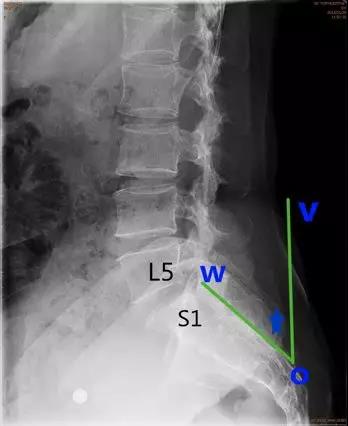

- 骶骨倾(斜)角:即S1后方骶骨后缘平行线与地面垂线之间的夹角。正常值<30°。

临床意义:>30°提示滑脱进展的风险。